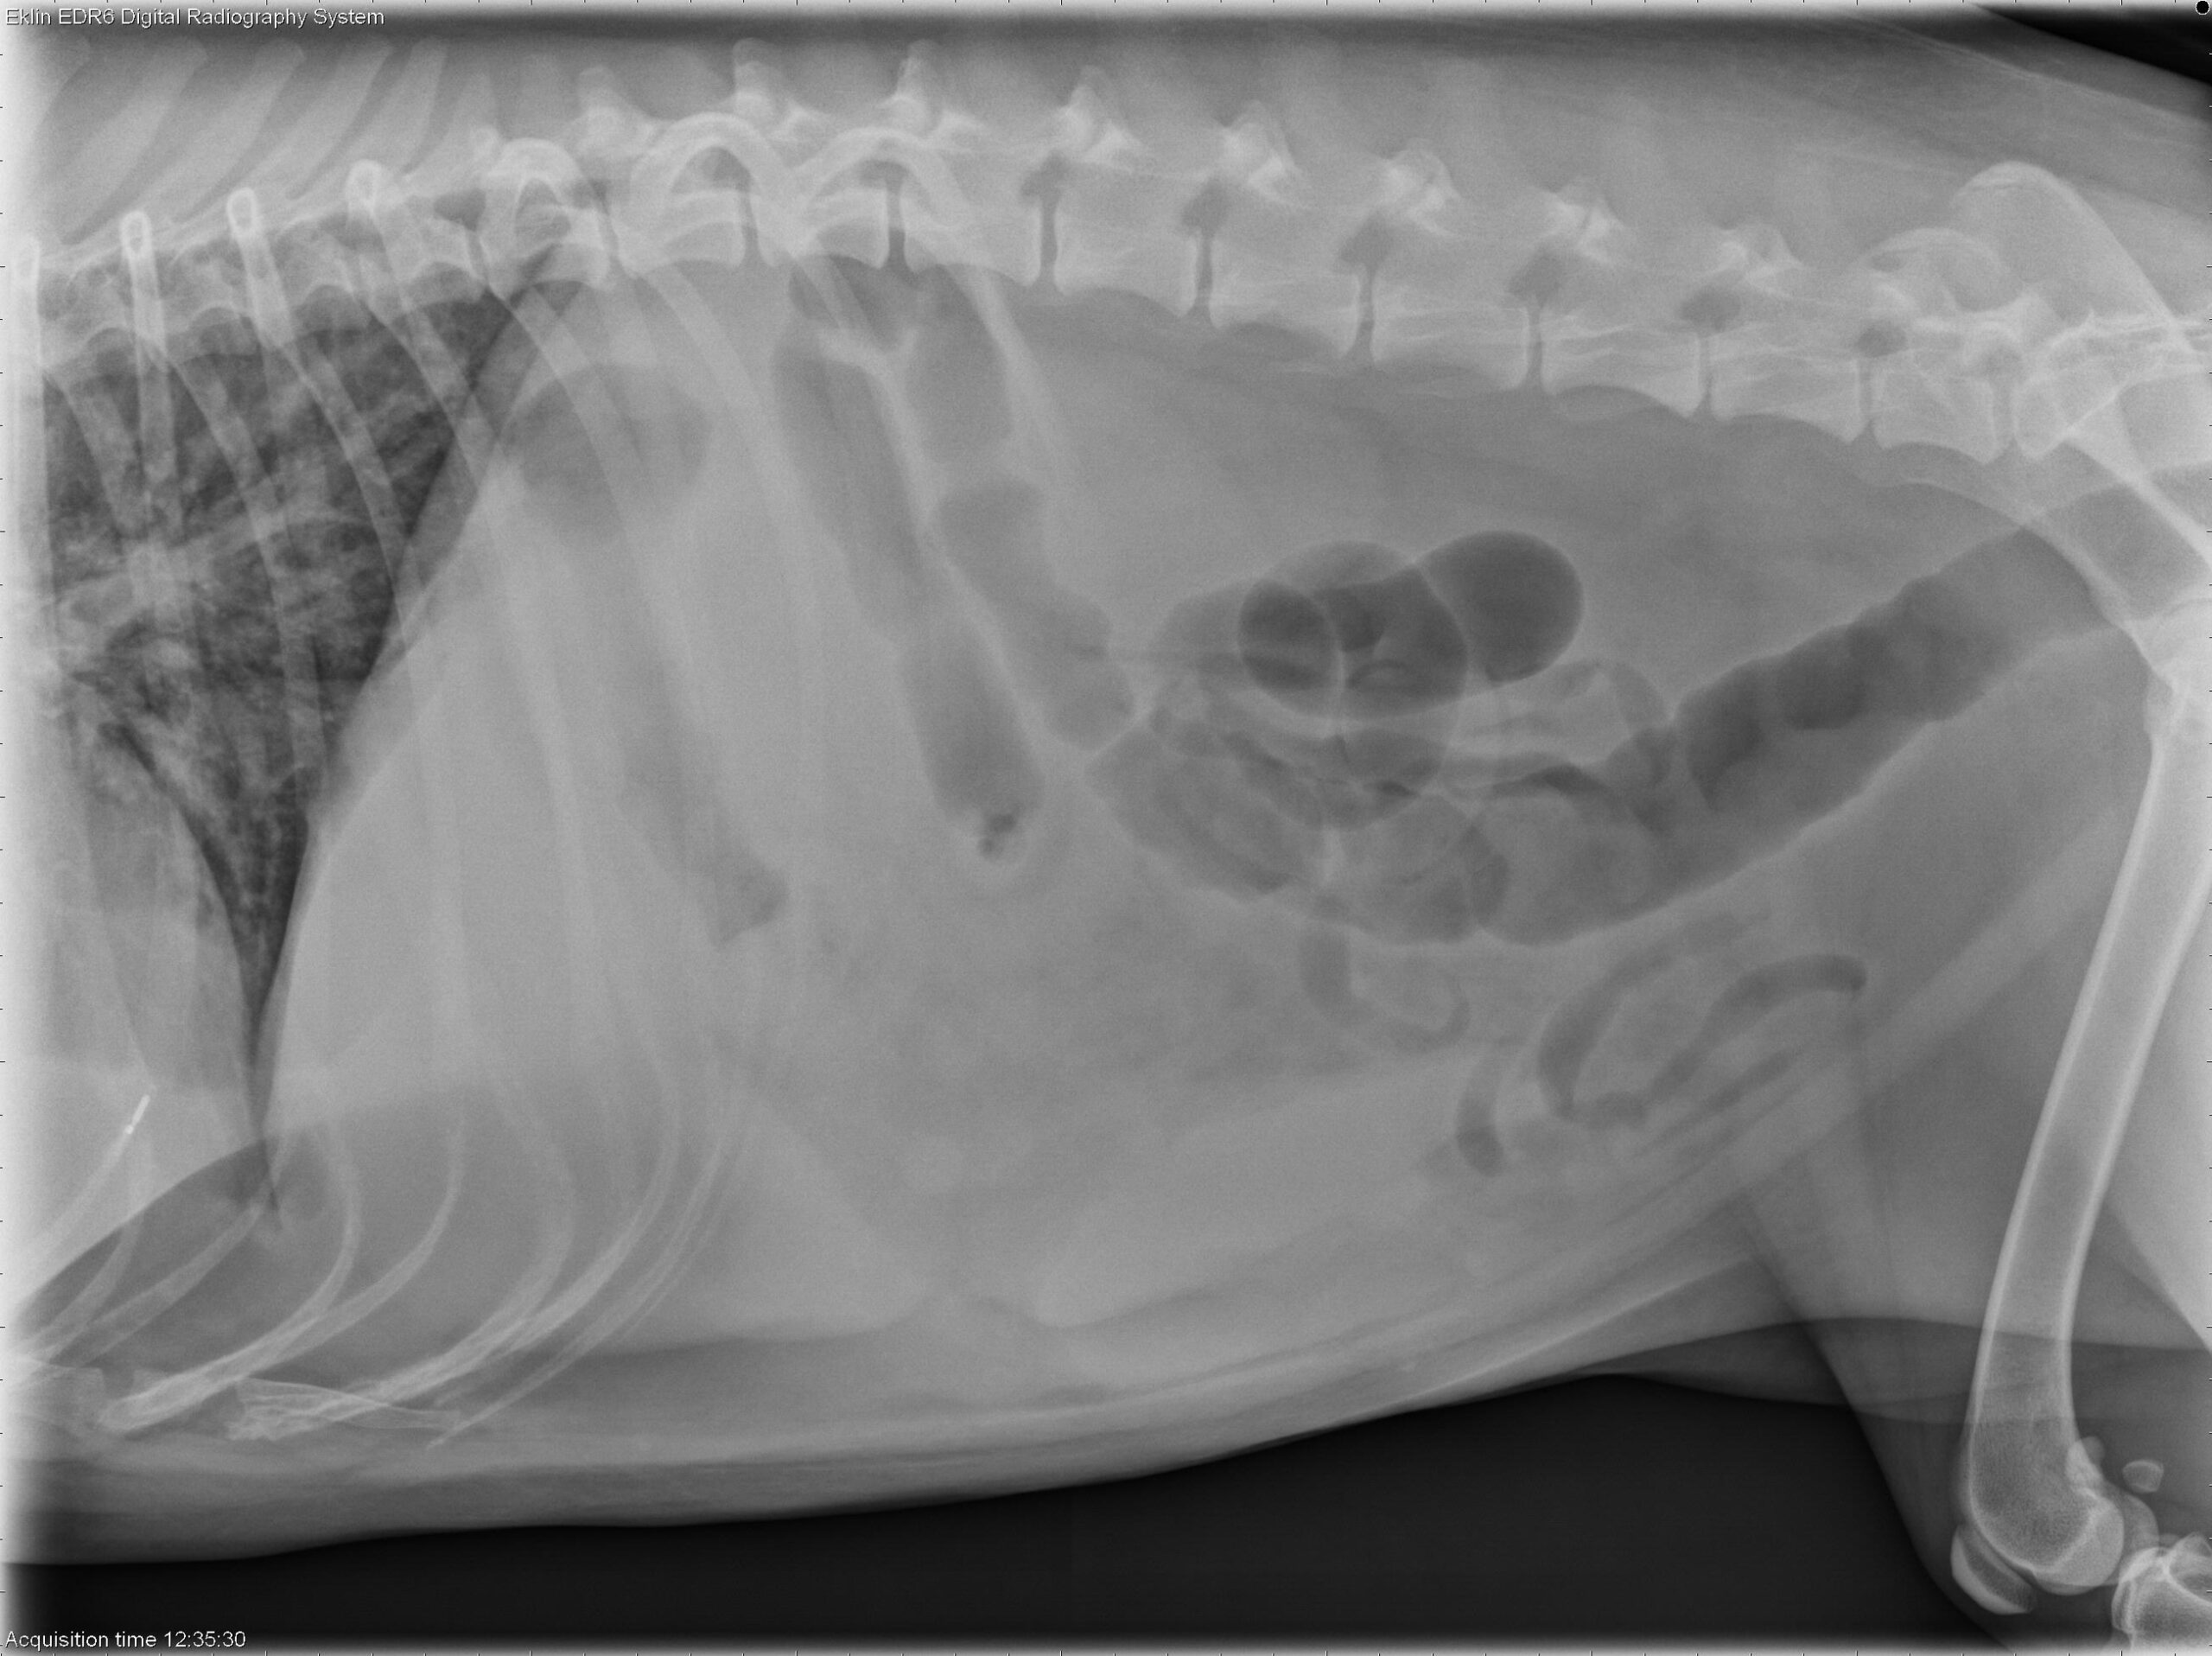

A 4-year-old spayed female Labrador Retriever is presented with fever of unknown origin (FUO).

Abdomen: The abdomen is distended with poor peritoneal detail. The liver and spleen are enlarged with rounded margins. The colon is moderately distended with gas. The small intestines appear normal. The urinary tract is poorly visualized.

Bicavitary effusion may result from round cell neoplasia, metabolic disorders, or inflammatory diseases. The hepatosplenomegaly is most suggestive of lymphoma. Differential diagnoses for the pulmonary pattern include lymphoma and non-cardiogenic pulmonary edema.

Ultrasound-guided fine-needle aspirates of the liver and spleen were obtained. Cytology confirmed hepatosplenic large granular cell lymphoma (NK-cell type). Thoracic POCUS revealed the presence of pleural effusion and B-lines within the lung parenchyma, indicative of pulmonary fluid accumulation. This suggests concurrent involvement of the lungs, most likely due to non-cardiogenic pulmonary edema.